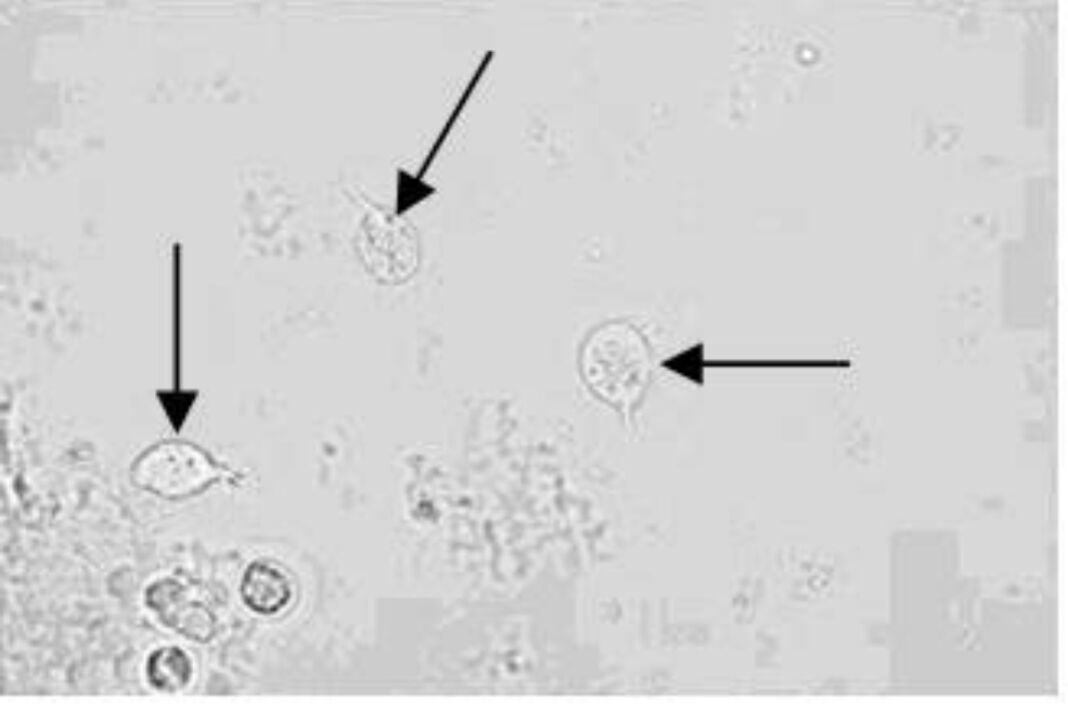

4.箭头所指目标:移行上皮细胞

8、箭头所指细胞内结构的名称:移行上皮细胞(深层)

9、箭头所指细胞内结构的名称:移行上皮细胞(中层)